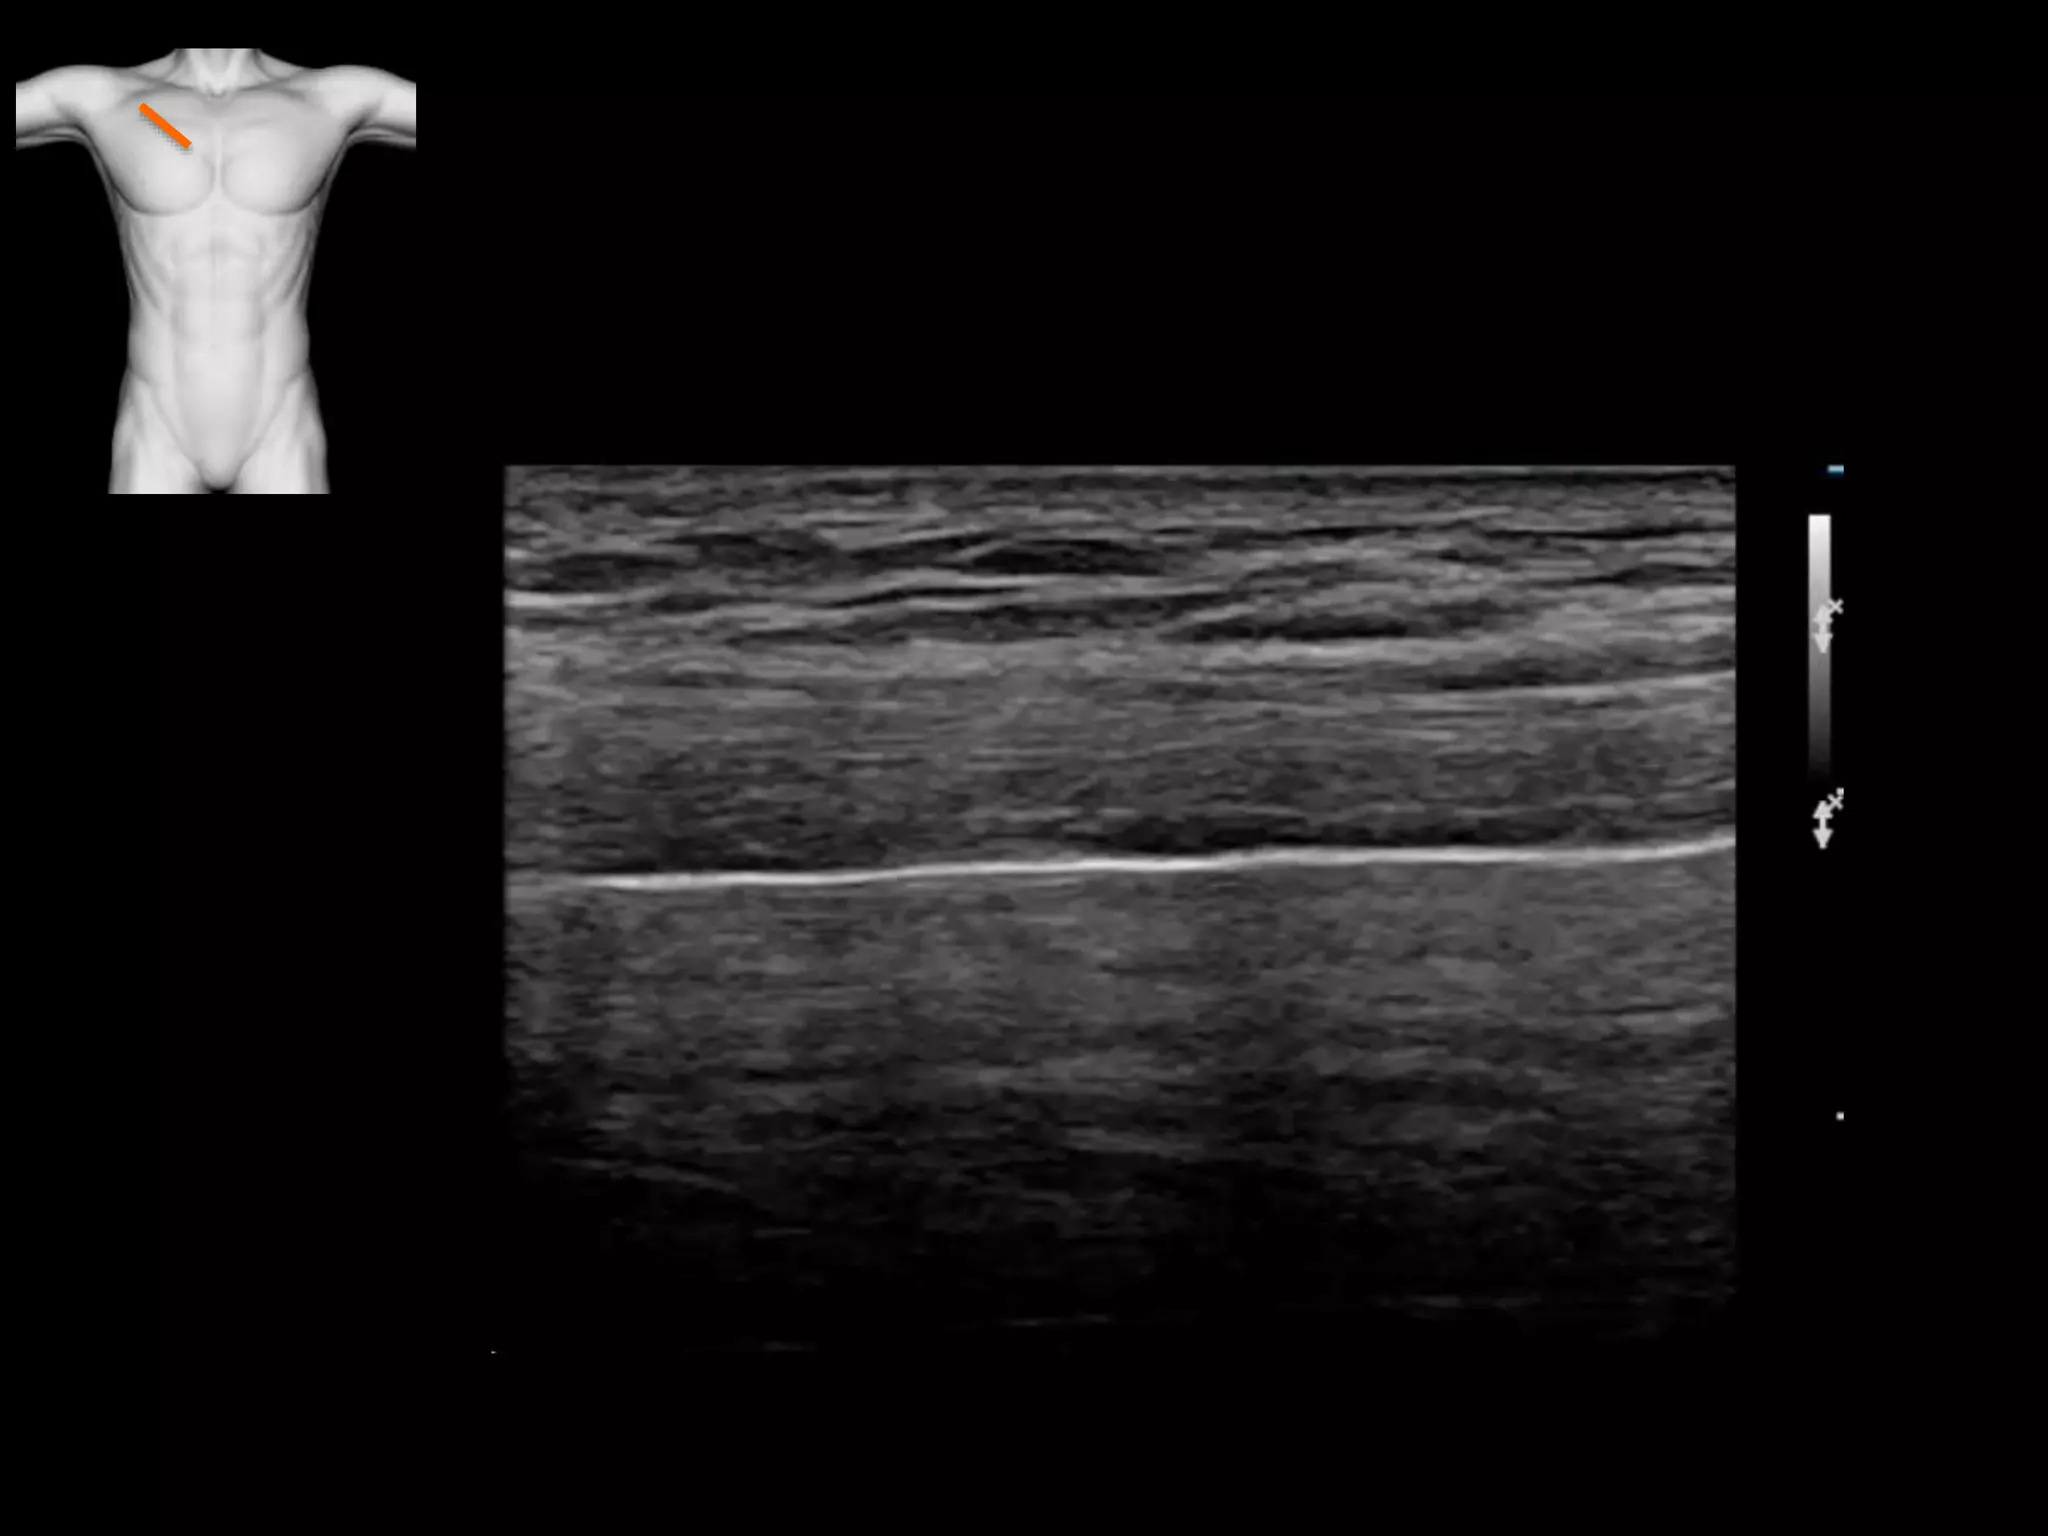

• This is a rib, you are on the long axis, it may

look like a pneumothorax

• This is sliding the transducer off the rib onto a

pleural space

• Hydropneumothorax